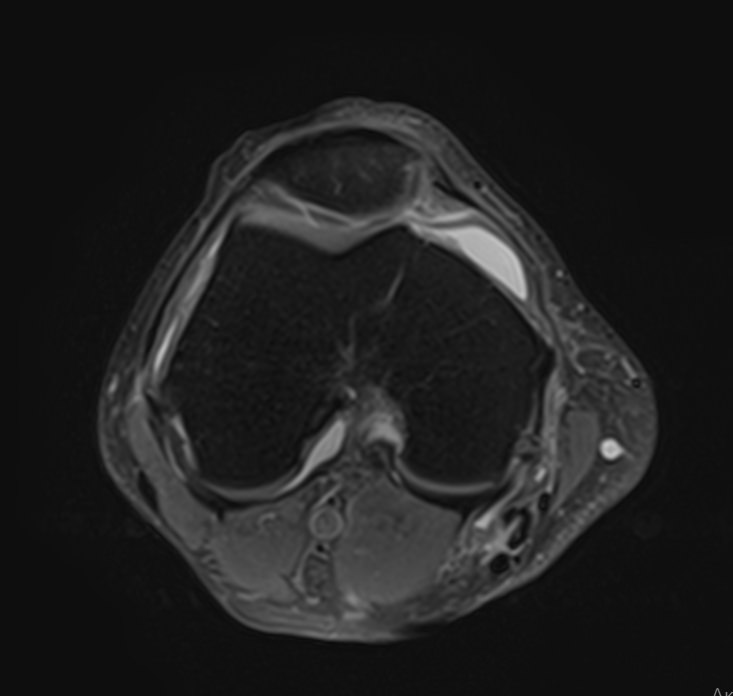

Магнитно-резонансная томография является современным высокоточным методом диагностики заболеваний опорно-двигательной системы человека. Во время исследования аппарат послойно сканирует анатомическую зону в различных плоскостях, затем с помощью компьютерных программ формирует трехмерные изображения с высокой точностью и достоверностью, что позволяет проводить эффективную диагностику заболеваний суставов.

Для выявления причин множественного поражения суставов в клинике «Доступная медицина» проводится комплексное обследование МРТ двух суставов, включающее два протокола исследования каждой анатомической области. При одностороннем поражении сустава также может назначаться МР сканирование одновременно двух симметричных сочленений для сравнения пораженной области со здоровым суставом на противоположной стороне. Это позволяет проводить более эффективную диагностику заболеваний суставов и назначать успешное лечение.

Какую патологию суставов можно выявить с помощью МРТ

• Из-за интенсивных нагрузок суставы часто подвержены травматизации (вывихи, подвывихи, внутрисуставные переломы, кровоизлияния в полости суставов – гемартрозы, растяжения, разрывы связок и сухожилий, ушибы мягких тканей),

• Воспалительные заболевания суставов (артриты, бурситы, синовиты, тендиниты, тендовагиниты).

• Дегенеративно-дистрофические заболевания суставов (артрозы, остеоартрозы).

• Врожденные аномалии развития (дисплазии, различные деформации и др).

• Выявление доброкачественных новообразований, например, кист и злокачественных опухолей (как первичных, так и метастазов).

• Обнаружение сосудистых заболеваний, поражений нервных волокон, патологии окружающих сустав мягких тканей.